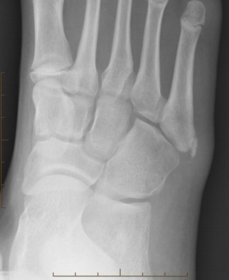

| What disease is this? | Gout |